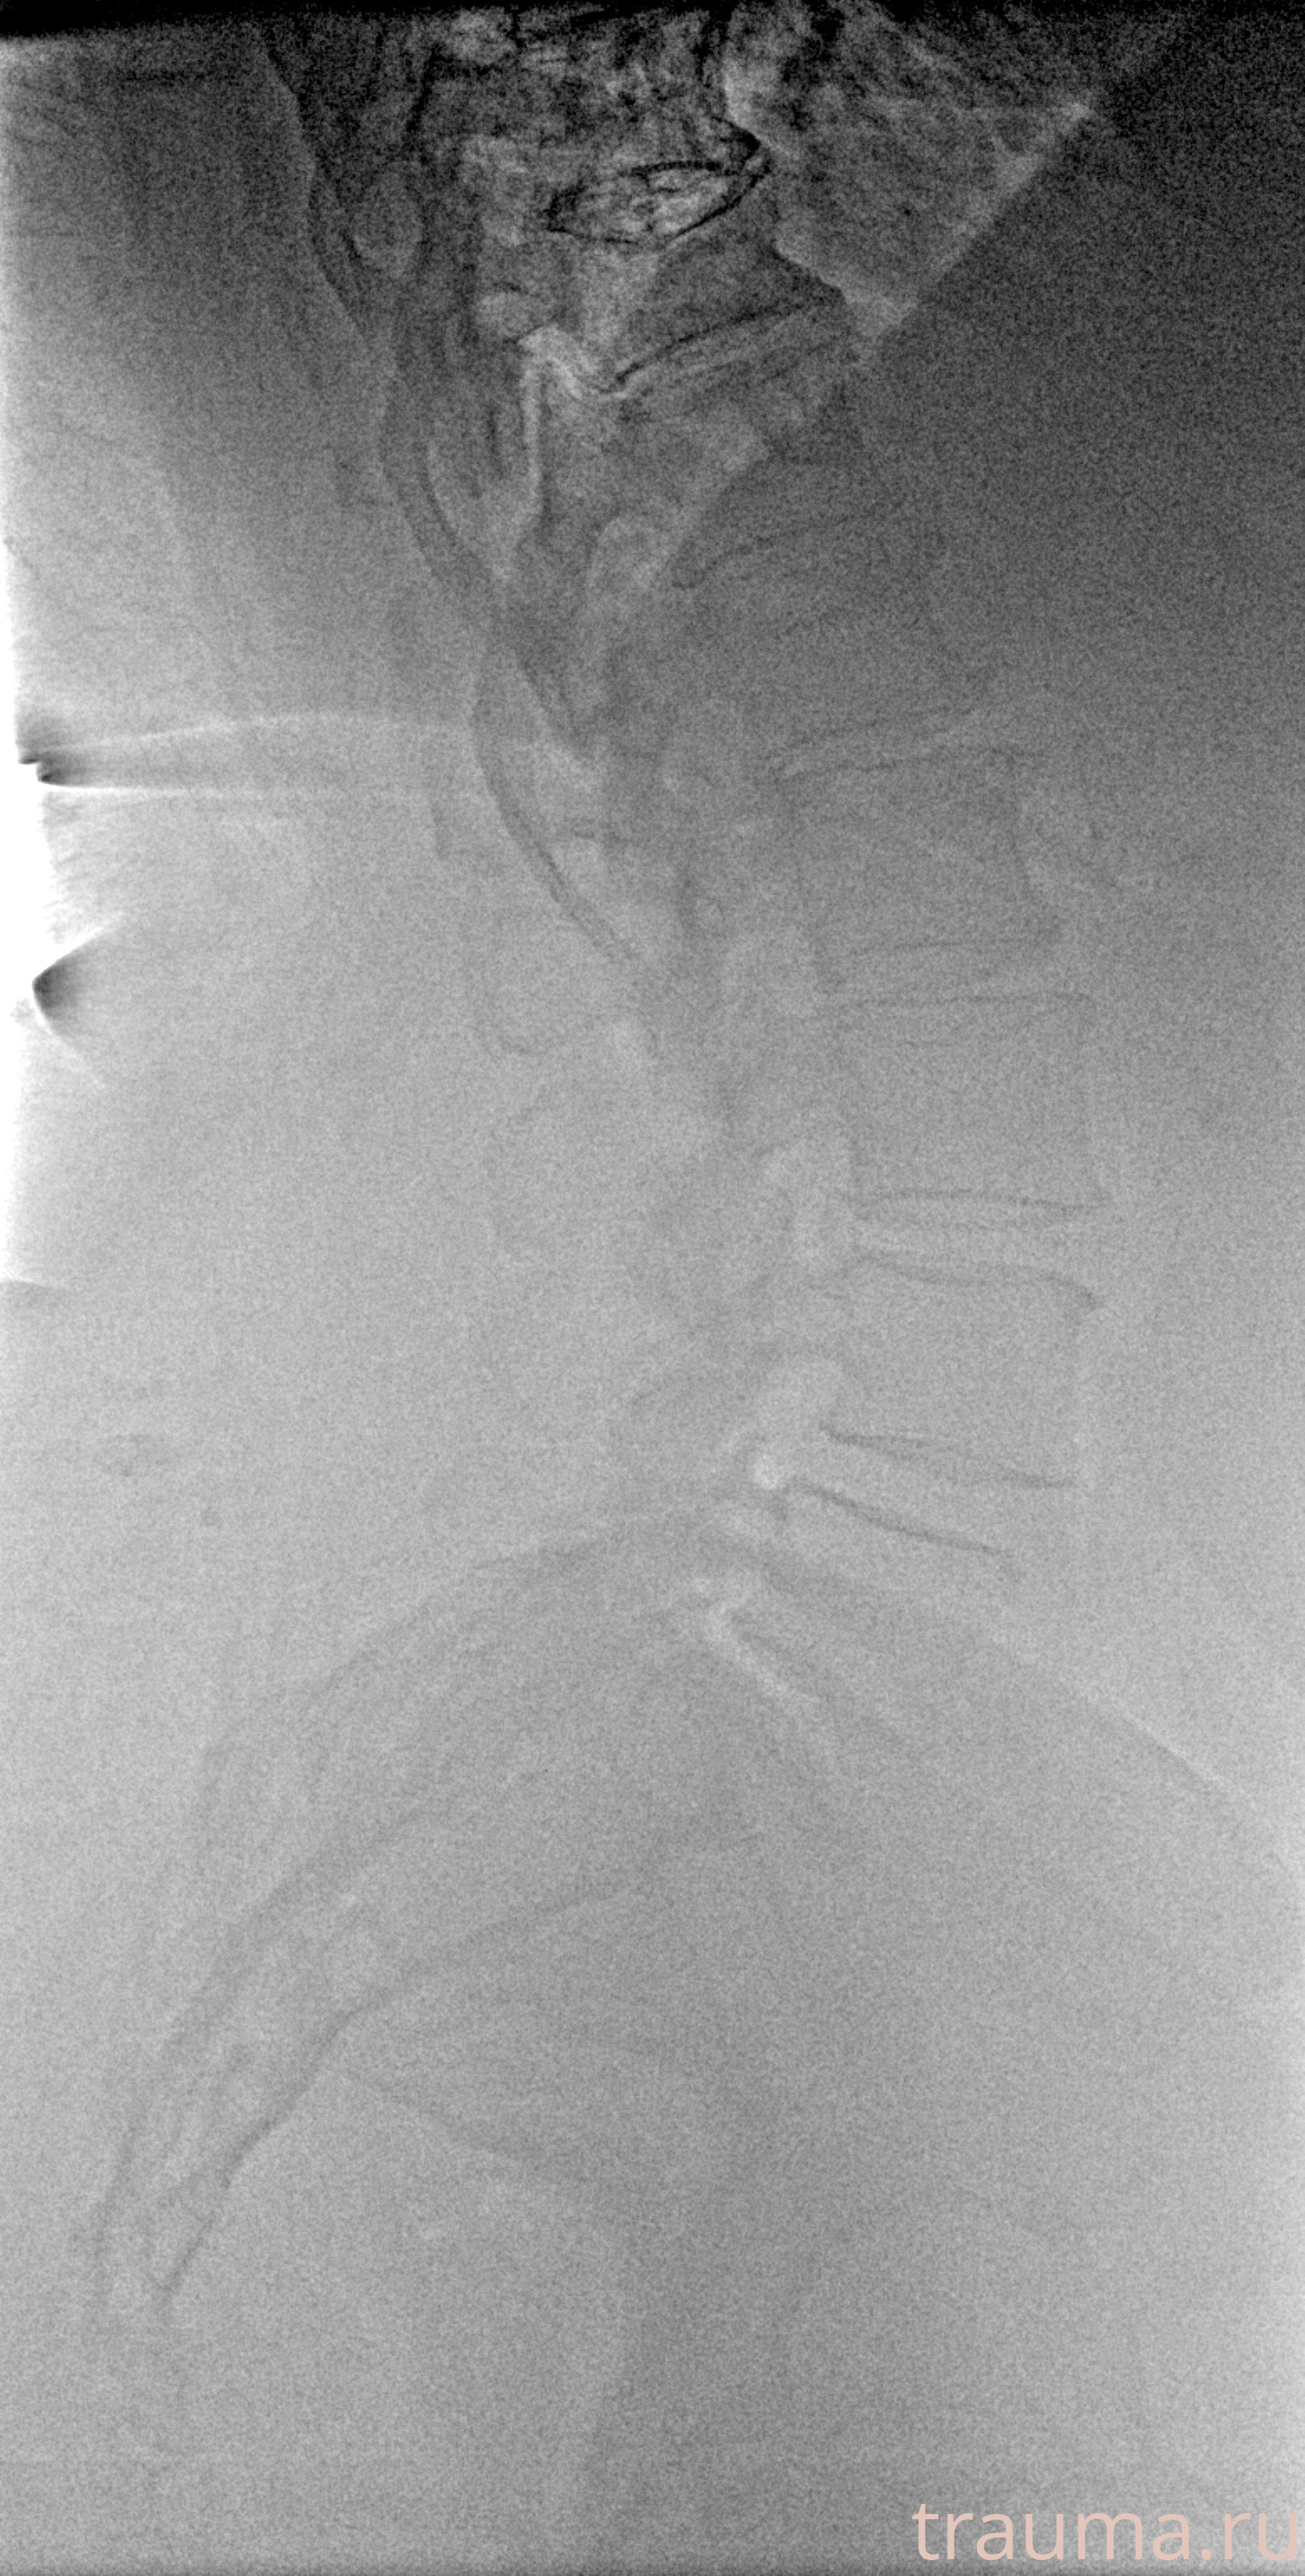

Рентген на дому: по вашему адресу приезжает врач-рентгенолог, травматолог-ортопед с мобильным рентгеновским аппаратом, проводит диагностику травмы или заболевания, делает необходимые рентгенограммы, дает рекомендации по дальнейшему лечению. Получить качественные снимки в домашних условиях возможно благодаря уникальной методике, разработанной МосРентген Центром для института  Склифосовского